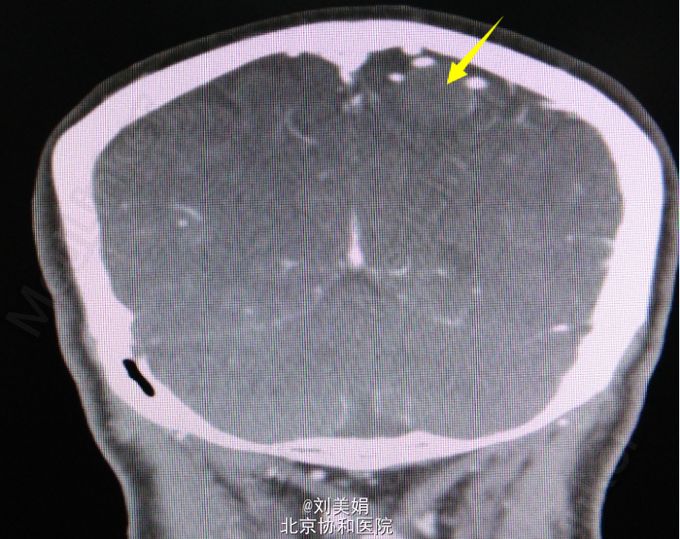

头增强CT:平扫图象显示:左侧顶部见一圆形略高密度影,边缘光整,边界清晰,大小约28.2mm×23.7mm,CT 值 68.2Hu,其内未见钙化,周围脑回受压、塌陷,脑室系统无扩大,脑沟裂未见增宽。中线结构未见明显移位。 增强图象显示:病灶明显均匀强化。CT 值为 92Hu,密度均匀,边缘清晰。右侧筛窦密度增高。